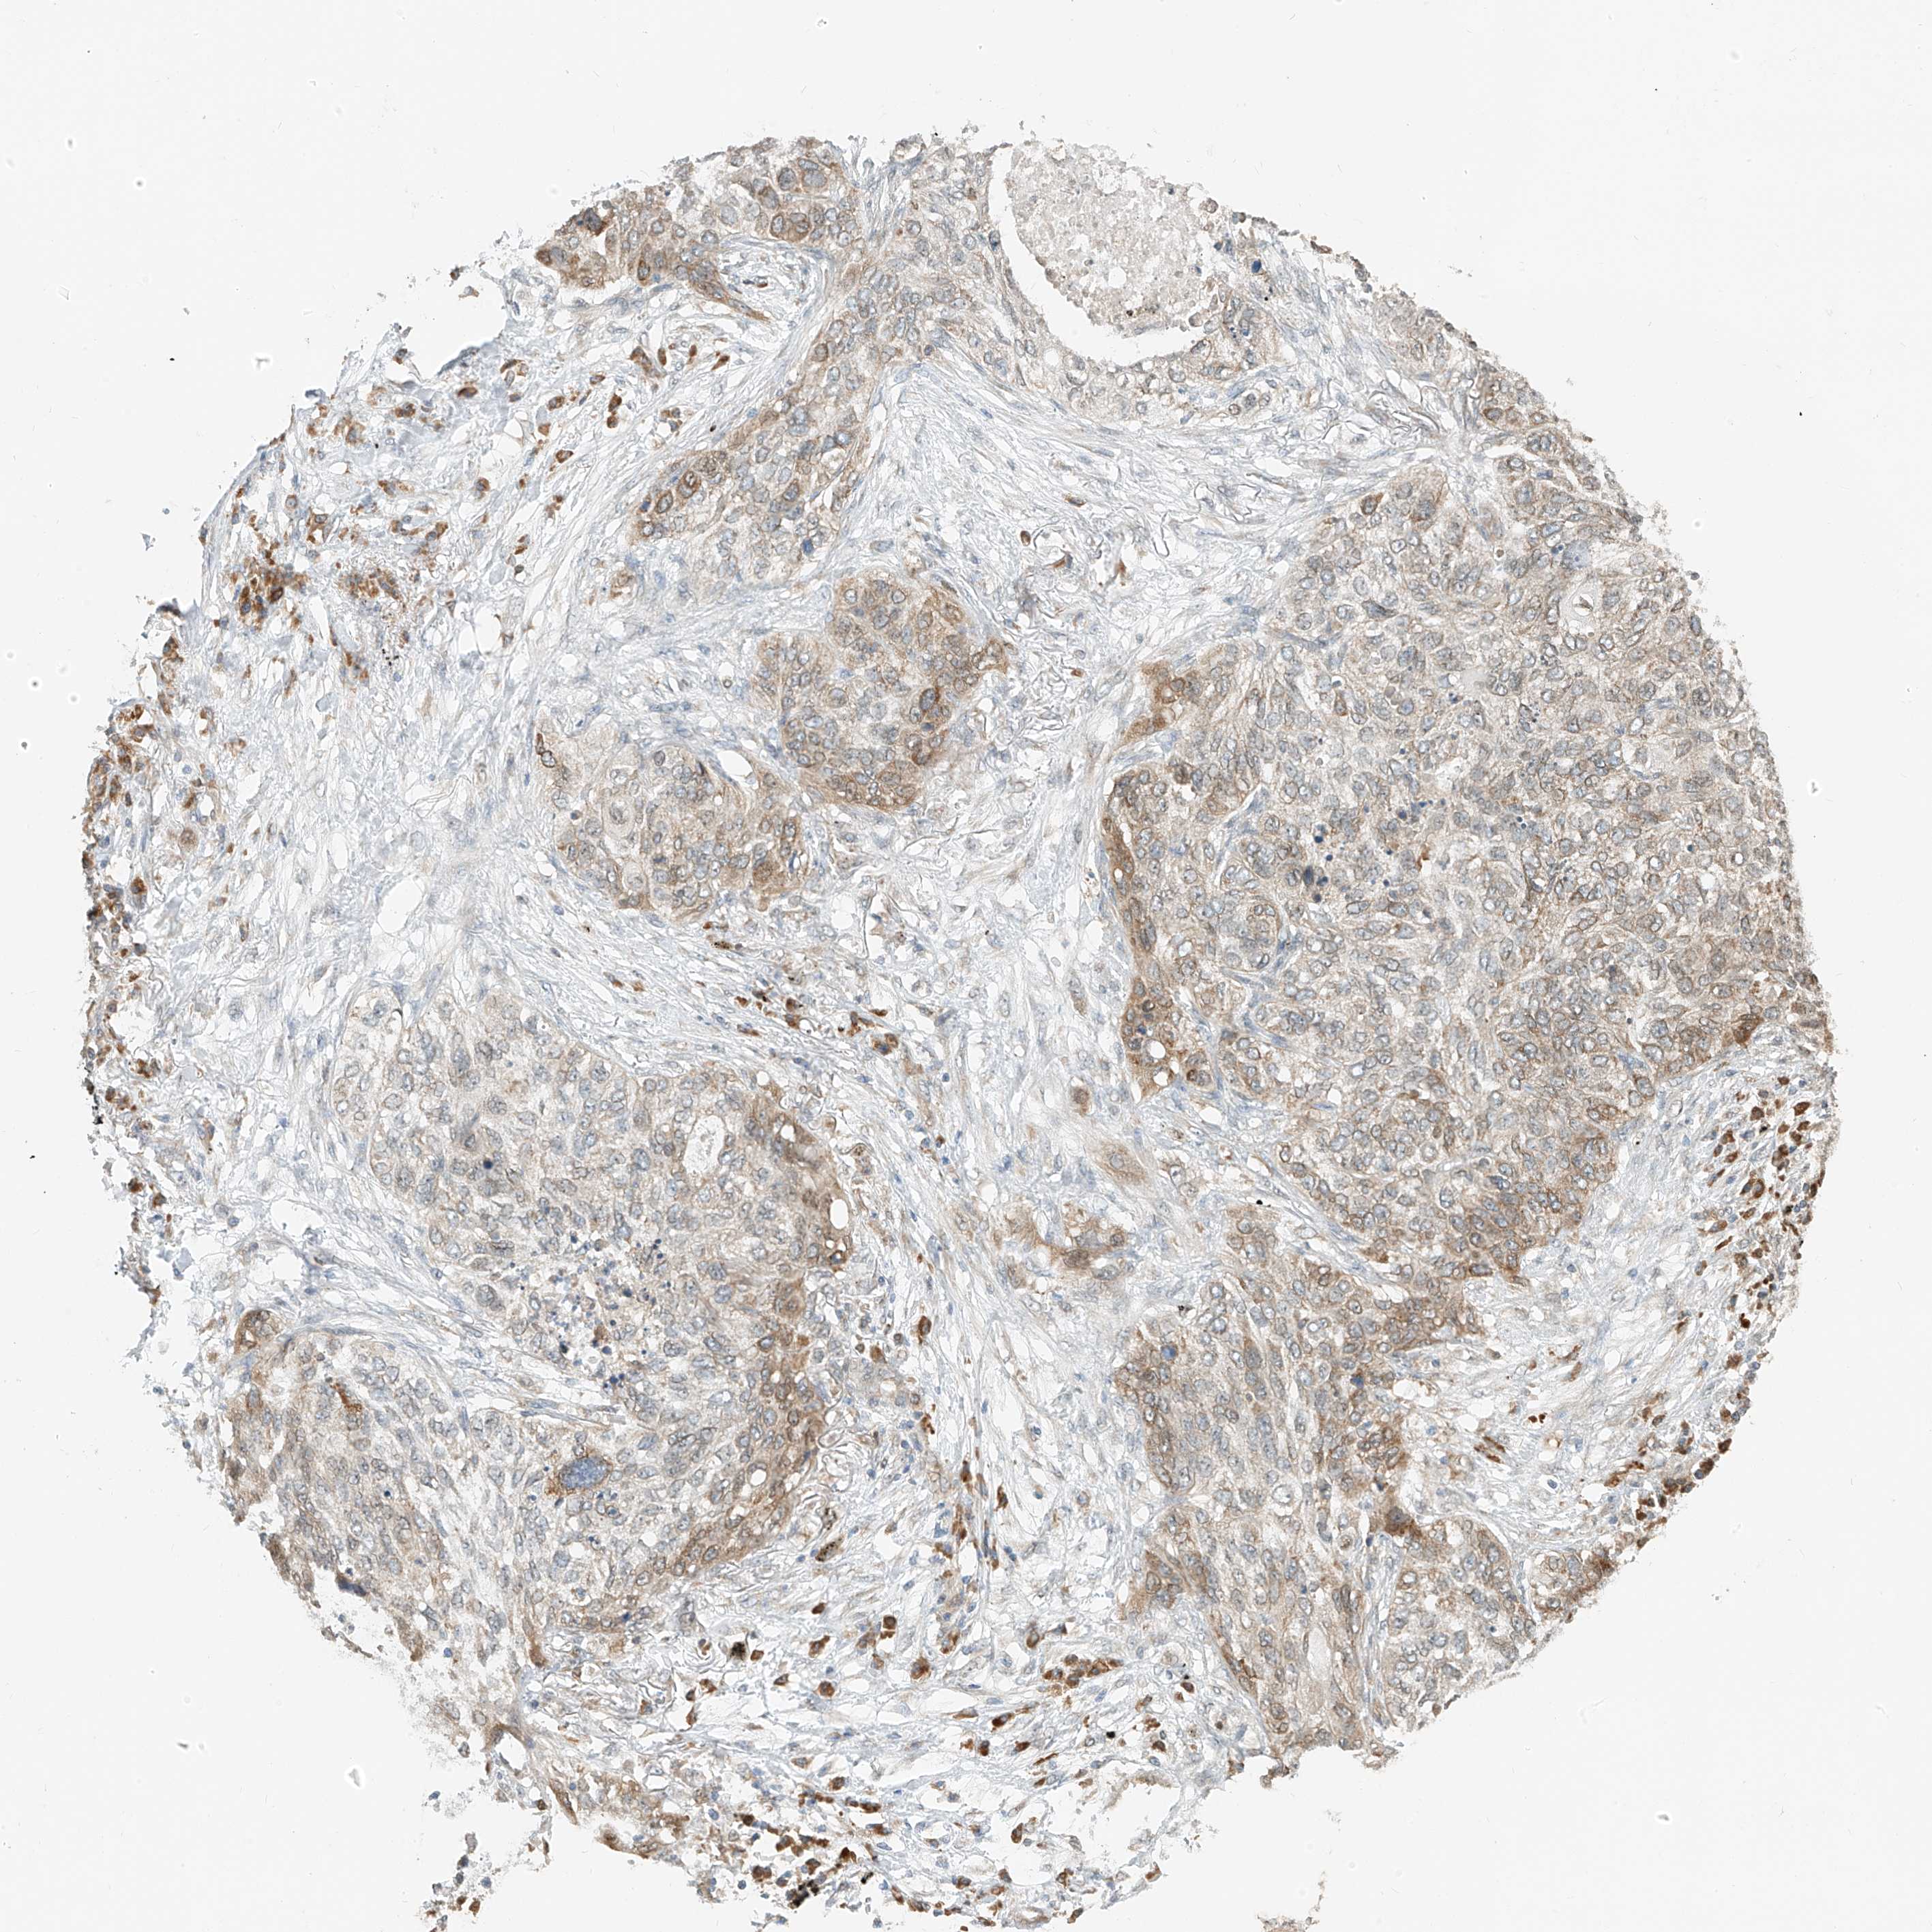

CANCER LUNG CANCER Show tissue menu

Lung cancer

Human cancer

Lung adenocarcinoma

Lung squamous cell carcinoma